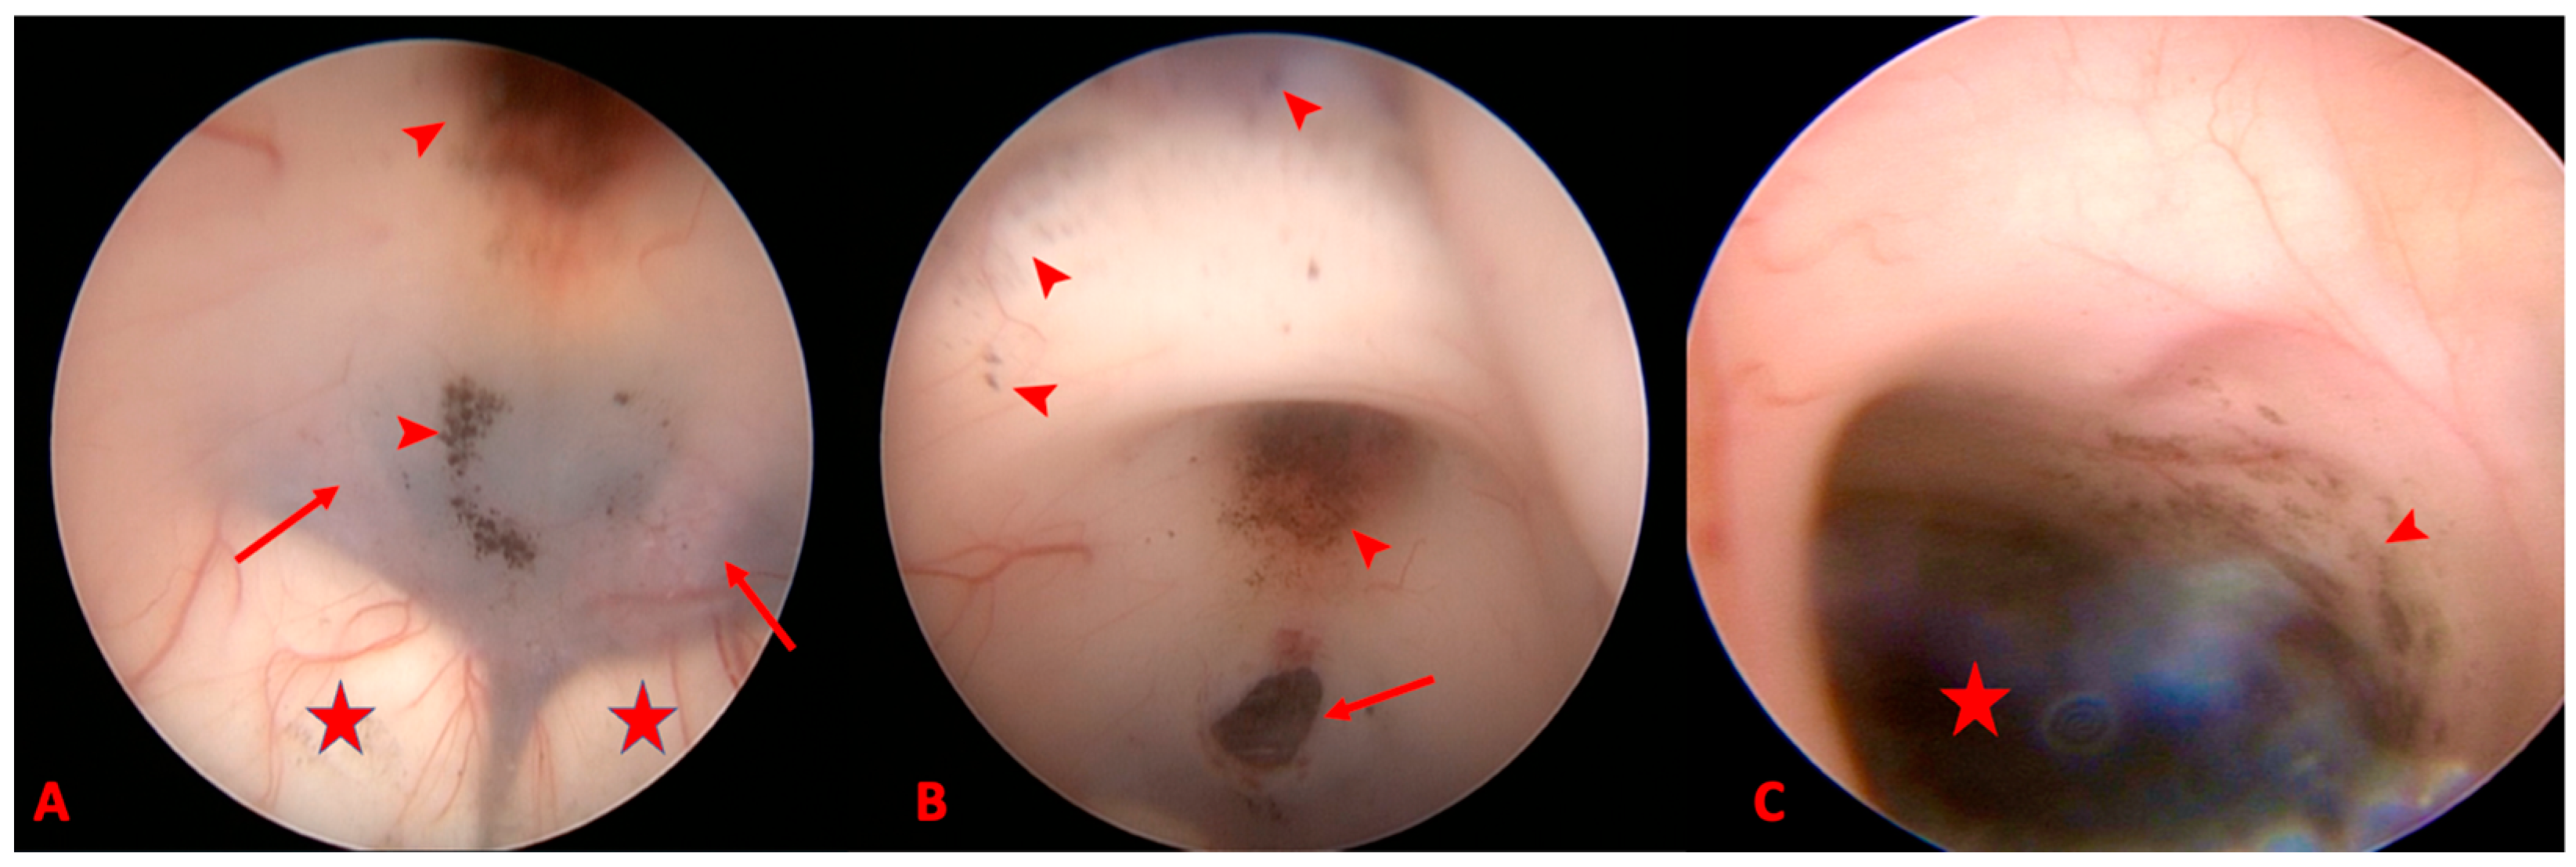

2. Detailed Case Description